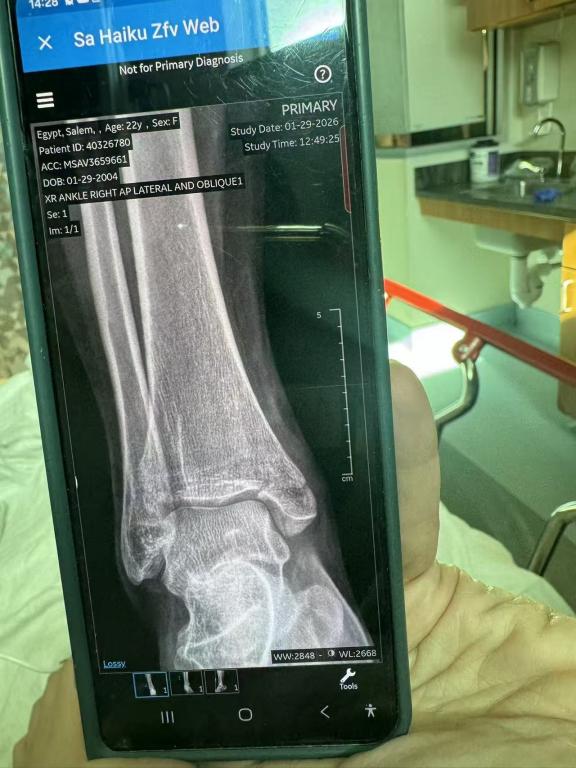

随后,救援团队第一时间与C女士取得联系,并迅速建立专属微信服务群,远程指导上传女儿的就诊记录、诊断报告和X光片。专业医护人员对伤情进行紧急评估,并持续指导后续就诊、复诊及休养安排。